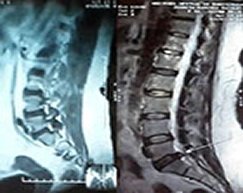

" Let your Medicine be your Food, and the Food your Medicine " ... Hipócrates " We are what we eat " ... Feuerbach " A Healthy Diet and Exercise, promote a Healthy Old Age " Treatment of Natural Origin Our provision of Health Services at a professional level in Medicine are granted individually by each one of us, and mainly help in the following Conditions: SPINAL DISC HERNIATION or SPINE HERNIATED DISC of VERTEBRAL COLUMN DEGENERATIVE OSTEOARTHRITIS or ARTHROSIS ( Osteoarthrosis - Cartilage Degeneration of the Joints ) OSTEOPOROSIS and OSTEOPENIA ( Decalcification and Demineralization of the Bones ) RHEUMATOID or RHEUMATIC ARTHRITIS. PREMATURE AGING GONARTHROSIS ( Degenerative Gonarthritis - Meniscus and Cartilages Degeneration of the knees ) and also in:

SCIATICA LOW BACK PAIN ( Backaches ) MIGRAINE ( Headaches ) FRACTURES OF VERTEBRAL COLUMN and others DISEASES OF ADULT MAJOR and AGING

SPORTS INJURIES ( Ligaments, Muscles, Tendons and Cartilages ) VERTEBRAL COLUMN DISEASES, REUMATHOLOGIC and CHRONIC-DEGENERATIVE ILLNESSES, among many others ...